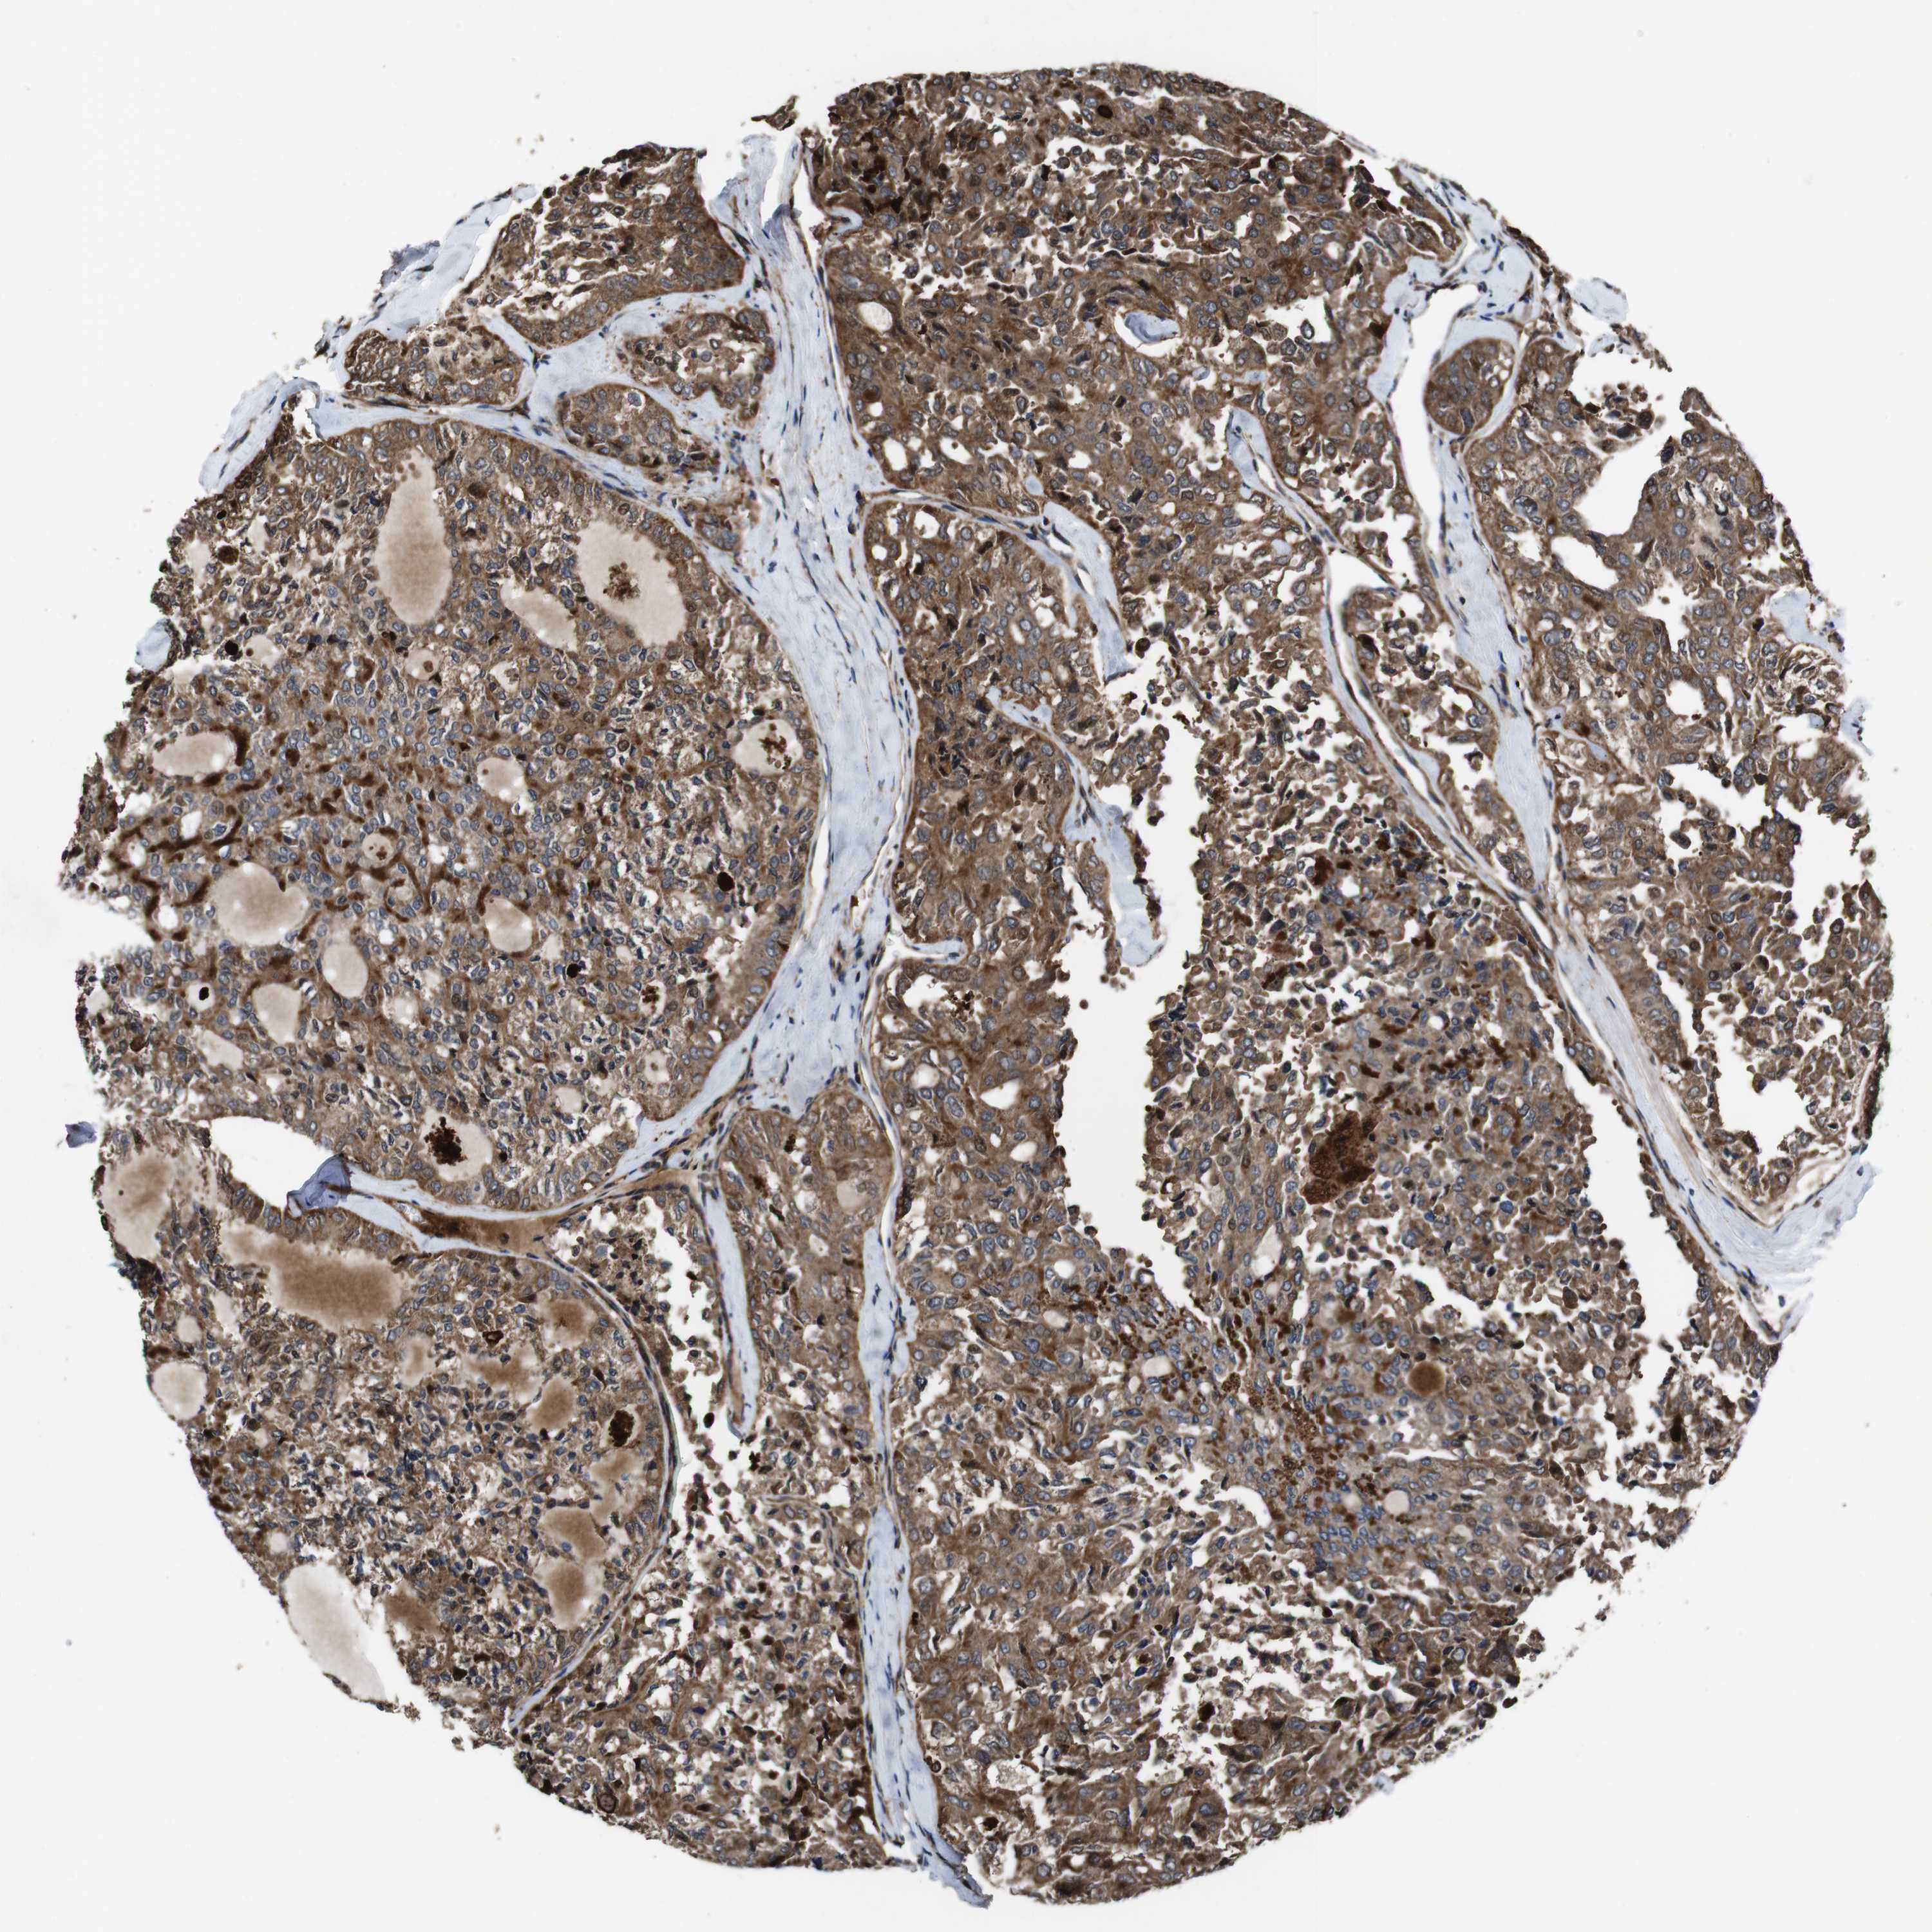

THYROID CANCER - Protein expressioni

A mouse-over function shows sample information and annotation data. Click on an image to view it in a full screen mode. Samples can be filtered based on level of antibody staining by selecting one or several of the following categories: high, medium, low and not detected. The assay and annotation is described here.

Note that samples used for immunohistochemistry by the Human Protein Atlas do not correspond to samples in the TCGA dataset.

Antibody stainingi

Antibody staining in the annotated cell types in the current human tissue is reported as not detected, low, medium, or high, based on conventional immunohistochemistry profiling in selected tissues. This score is based on the combination of the staining intensity and fraction of stained cells.

Each image is clickable and will lead to virtual microscopy that enables deeper exploration of all samples and also displays staining intensity scores, fraction scores and subcellular localization as well as patient and tissue information for each sample.

Antibody HPA045821

Antibody HPA054352

Antibody CAB012229

Staining

High

Medium

Low

Not detected

Intensity

Strong

Moderate

Weak

Negative

Quantity

>75%

75%-25%

<25%

None

Location

Nuclear

Cytoplasmic/membranous

Cytoplasmic/membranous,nuclear

Papillary adenocarcinoma, NOS

Follicular adenoma carcinoma, NOS